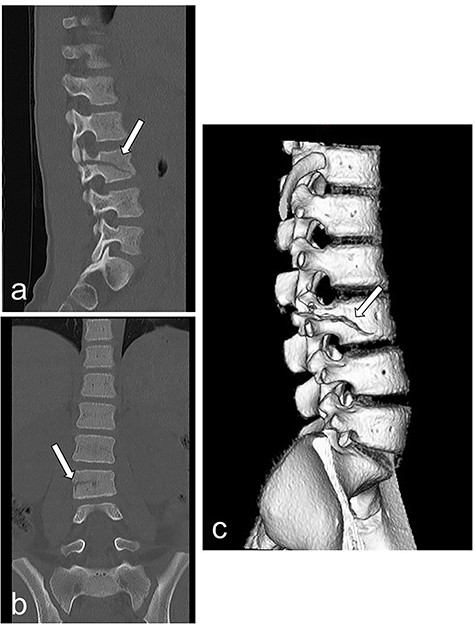

Laparoscopic inspection revealed purulent ascites with intestinal adhesions (Fig. 3a). The amylase level in the ascitic fluid was 8757 IU/L (Table 1). The intestine was pulled out through the umbilical wound, and a segment of the jejunum was confirmed to be ruptured (Fig. 3b and c). The involved 10-cm segment of jejunum was excised (Fig. 3d), and an end-to-end anastomosis was performed.

Intra-operative findings. (a–c) Exploratory laparoscopy reveals purulent ascites with intestinal adhesions and a ruptured jejunum. (d) A 10-cm segment of jejunum is excised.